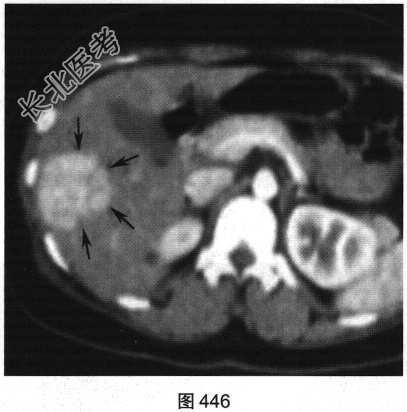

- 多项选择题2.[提示]患者行CT三期增强扫描,如图446~图448所示。对患者CT三期增强扫描图像描述正确的是( )

A、动脉期病灶明显强化

B、门脉期病灶无强化

C、病灶位于肝S5/6,边界清

D、延迟期病灶呈等密度

E、病灶为富血供肿瘤

F、门静脉期病灶为低密度